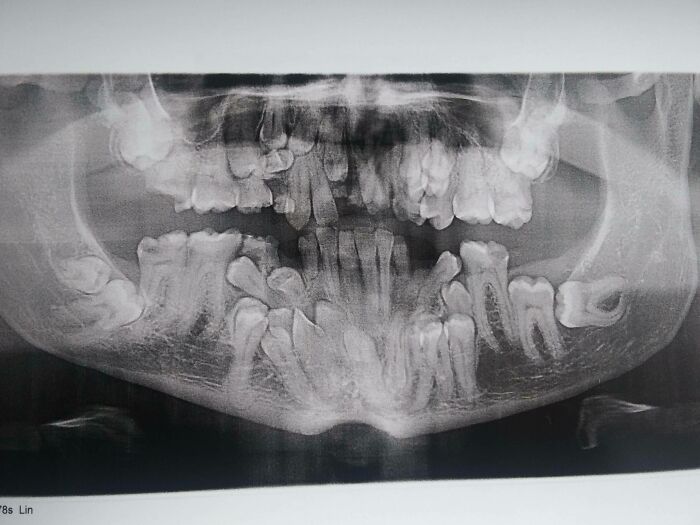

I Have A Rare Disorder Called Cleidocranial Dysotosis. Got My First Dental X-Ray Today And I Have A Lot Of Extra Teeth